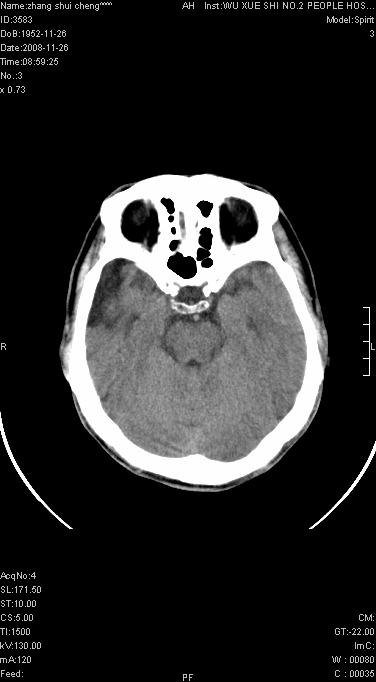

标题: CT16800:男.68.肢体无力多年请会诊 [打印本页]

男.68.肢体无力多年

请问是蛛网膜囊肿.还是软化灶.原有中风

支持右侧颞区蛛网膜囊肿。

蛛网膜囊肿,软化灶周围脑沟应该受牵拉,扩大

颞部膨胀,多考虑蛛网膜囊肿